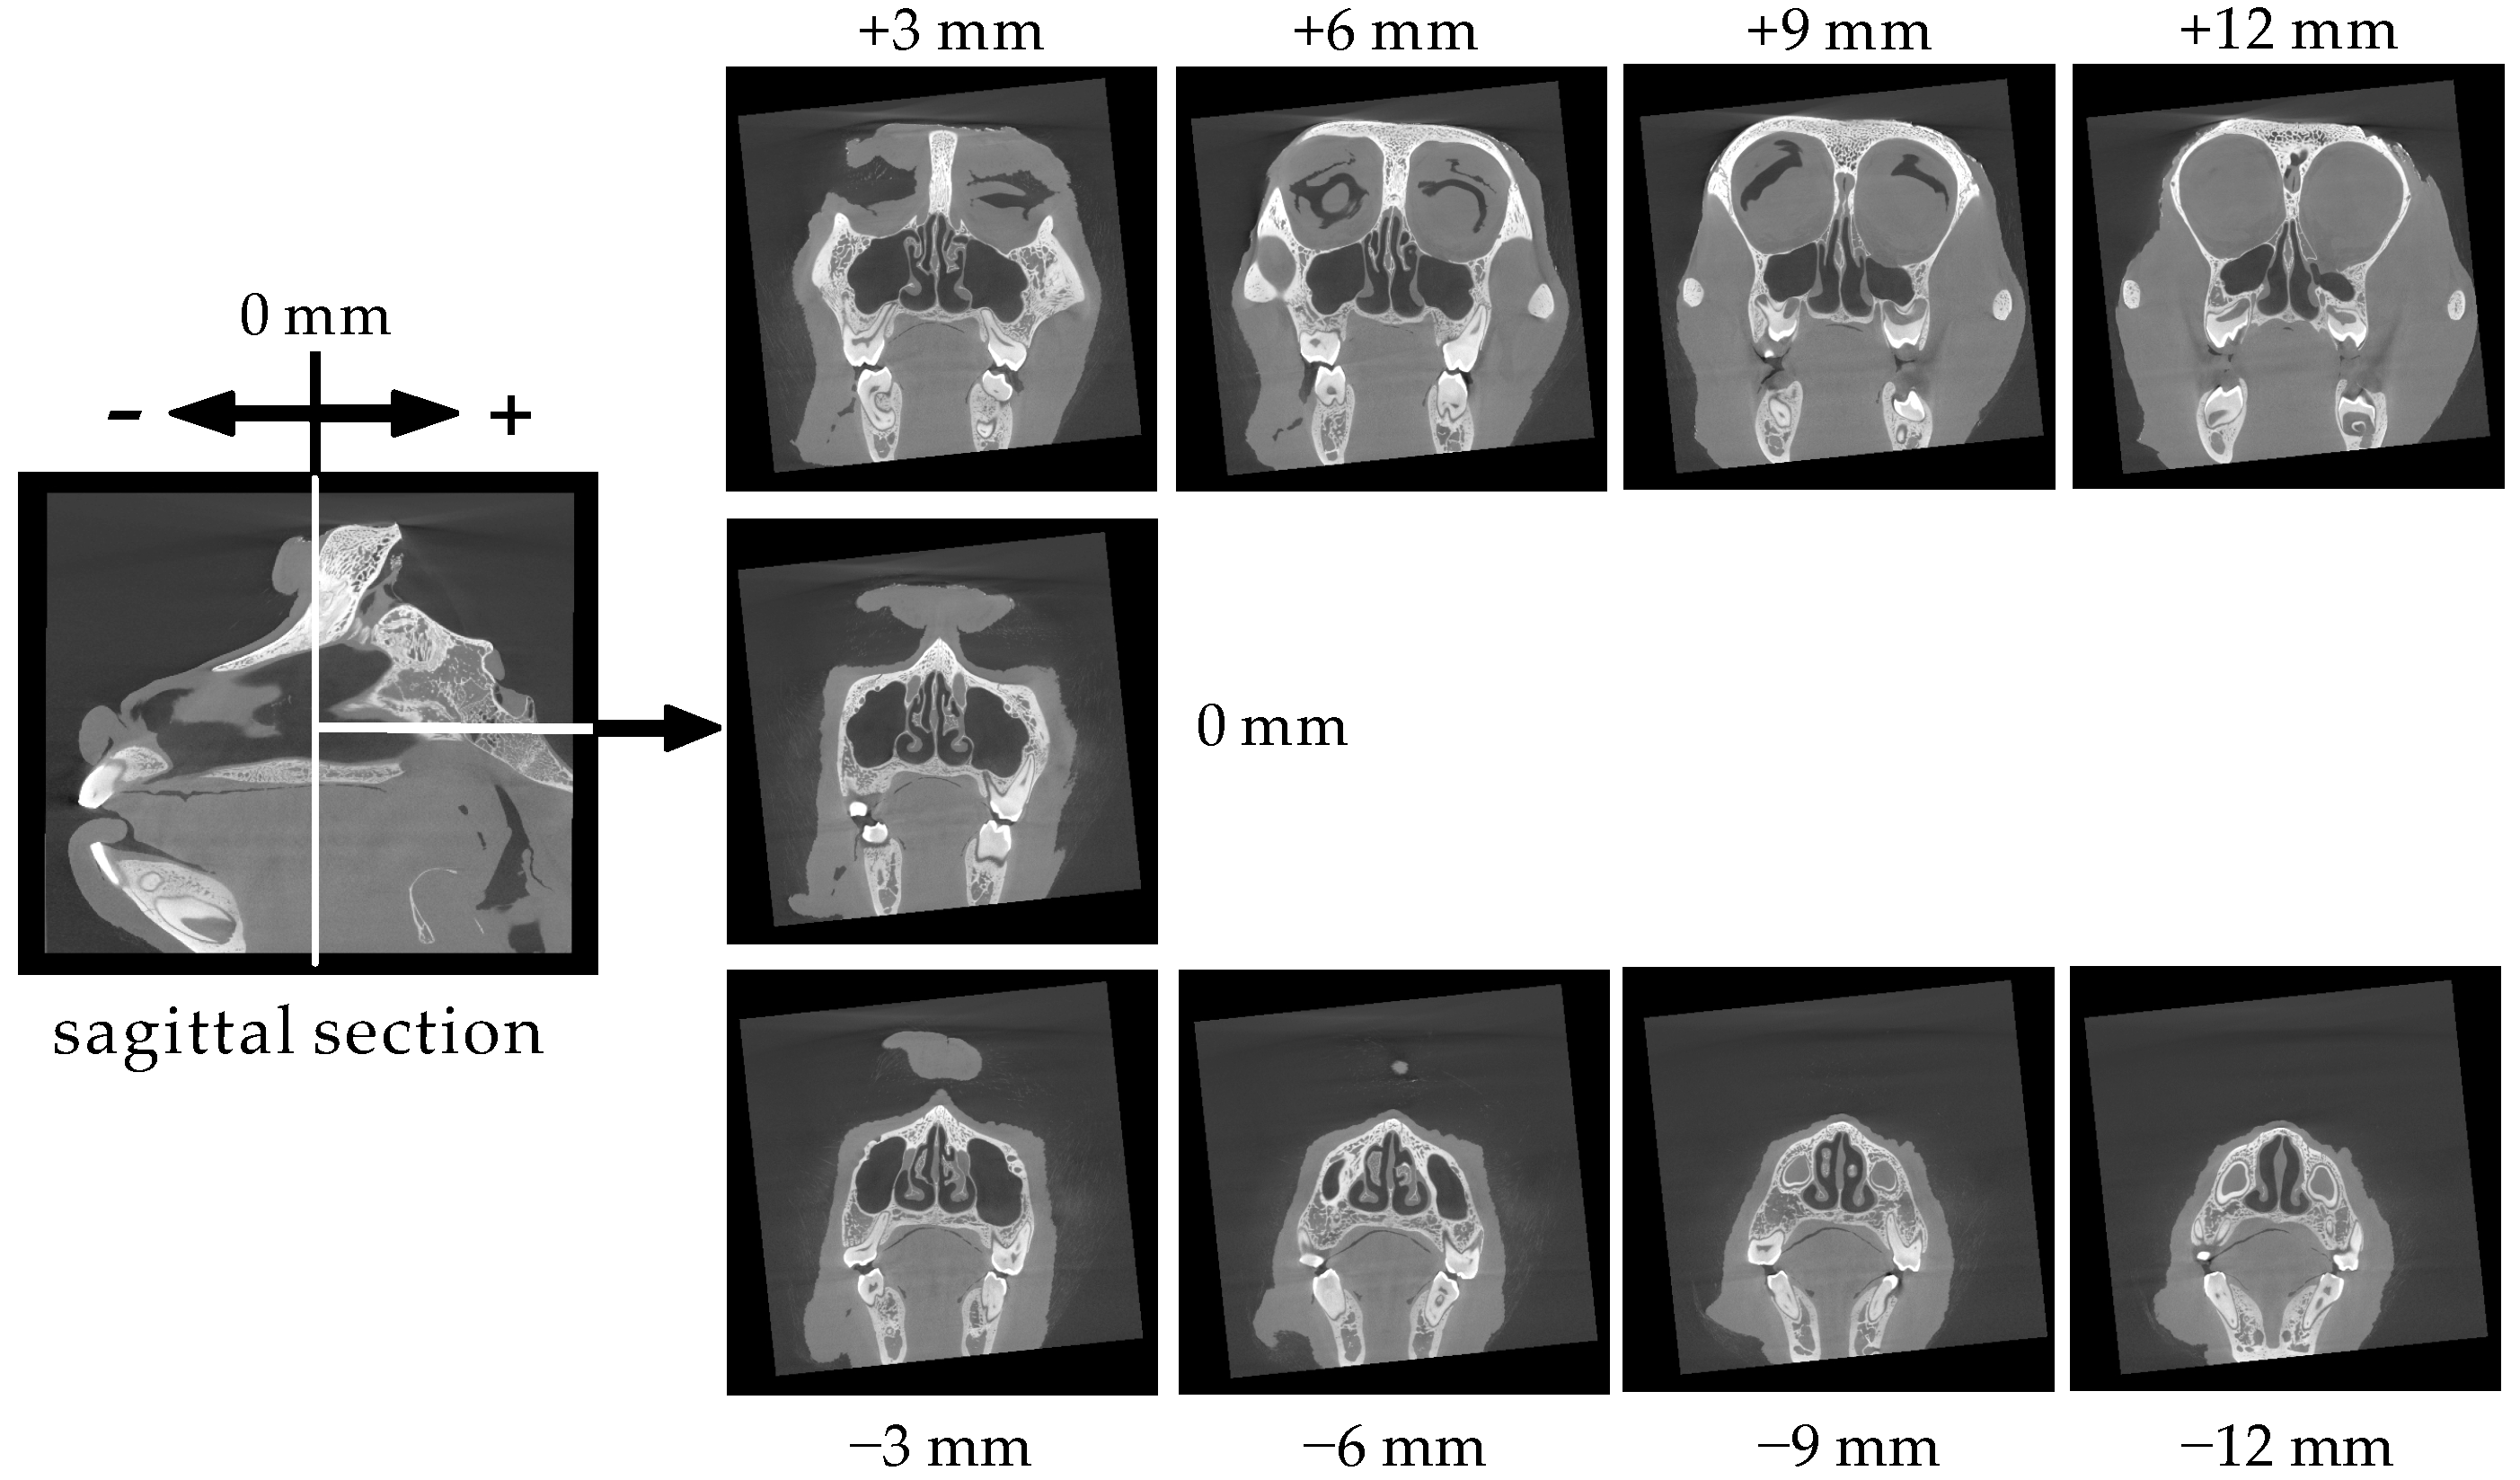

3.1. Structure and Size of the Cynomolgus Monkey Nasal Cavity

3.2. Size of the Nasal Cavity and Relative Position with the Brain